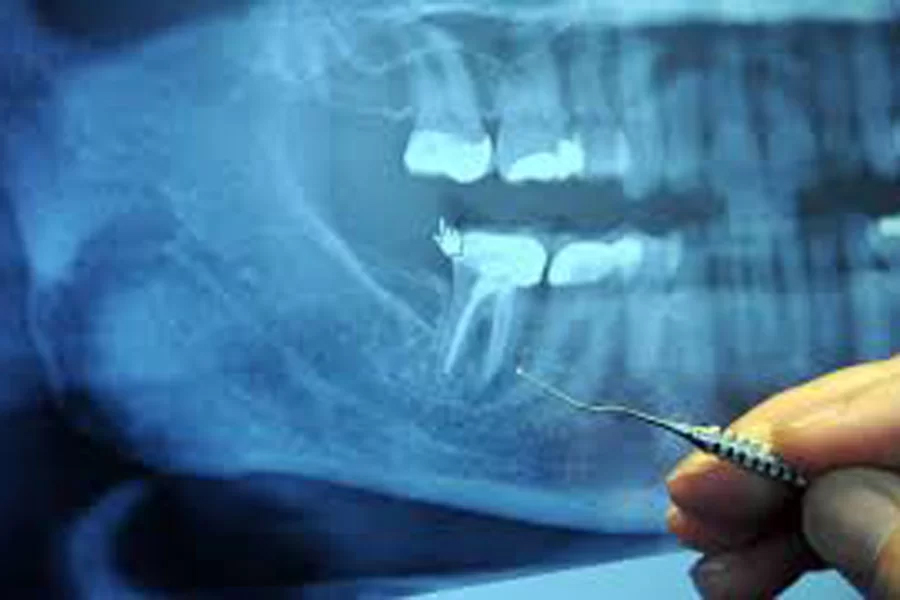

レントゲン写真では、親知らずの歯がどのように顎の骨に埋まっているのか、神経が親知らずと接触しているかどうかの確認が正確に行えないため、CT撮影をして親知らずの埋まり方や歯根の形、神経や血管との距離など正確に診断する必要があります。

また歯茎に埋まっている親知らずや横向きに生えている親知らずも、根の先と下顎管が近接しているケースが多いため、抜歯の際にはCT撮影による事前の綿密な診査診断がとても重要です。